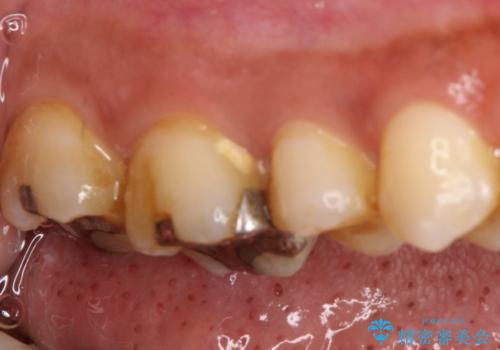

- 左上の奥歯がズキズキ痛い、冷たいものも長引く痛みがあると来院されました。

根管治療を行った後にオールセラミッククラウンにて修復しております。

根管治療を行った場合、破折リスクを軽減するために被せ物を行っております。